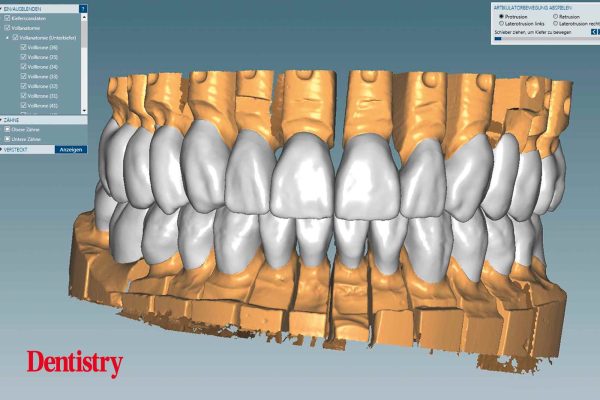

Fabrication and cementation of crowns without chipping – part two

Peter Antosch ODT and Dr Carsten Hörr present a bruxism case whereby full mouth crowns are CAD/CAM manufactured and then…

Laboratory

Fabrication and cementation of crowns without chipping – part one

Peter Antosch ODT and Dr Carsten Hörr present a bruxism case whereby full mouth monolithic crowns are CAD/CAM manufactured and…

Laboratory